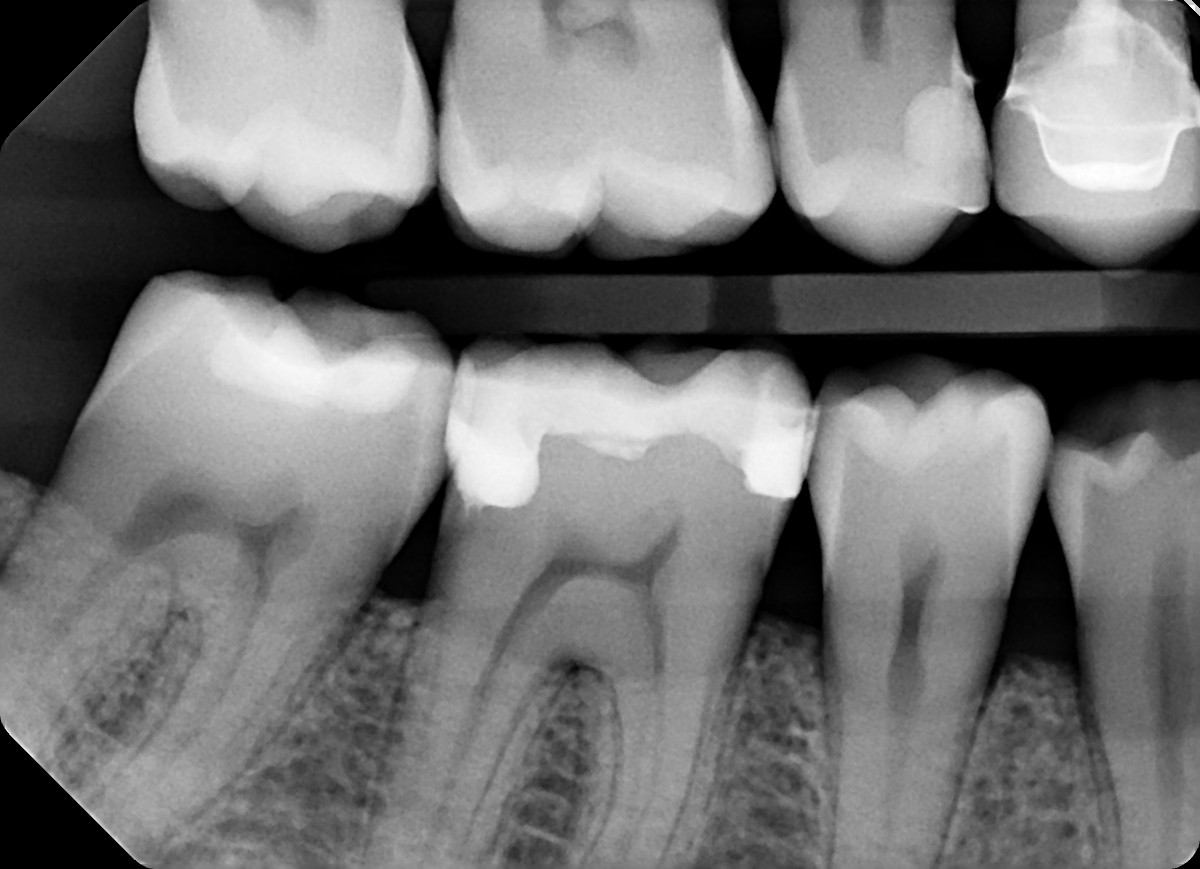

1. On which surface a recurrent caries can be detected?

2 / 35

2. On which surface a recurrent caries can be detected?

None of the teeth shows recurrent caries